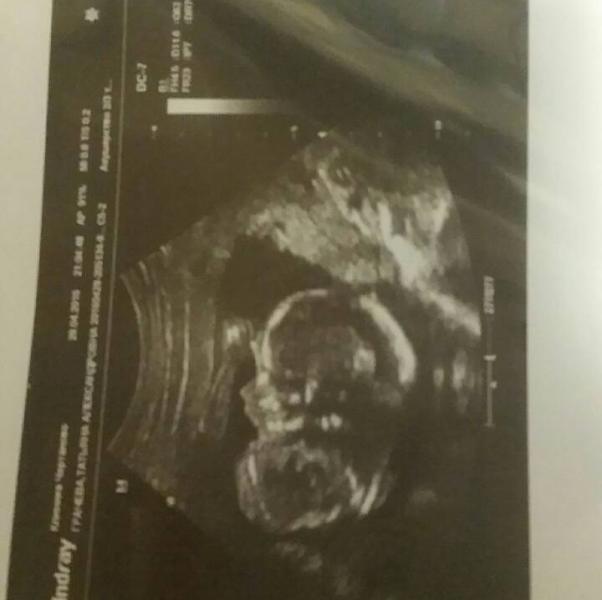

побежала сегодня к платному гинекологу, как увидела кровь в туалете, ну я сразу поняла, что это геморрой, мать его 😠, но мне надо было удостовериться естественно, послала к проктологу, но заодно сделала узи, чтобы проверить все ли там в порядке)

малыш, конечно, гимнаст тот еще.как-то умудрился засунуть голову между ног, так смешно было это наблюдать 😃

когда врач предположила пол, сказала, что похоже больше на девочку, но гарантию не дает, то в это время малыш показал кулак👊😂 сказала, что носик ...